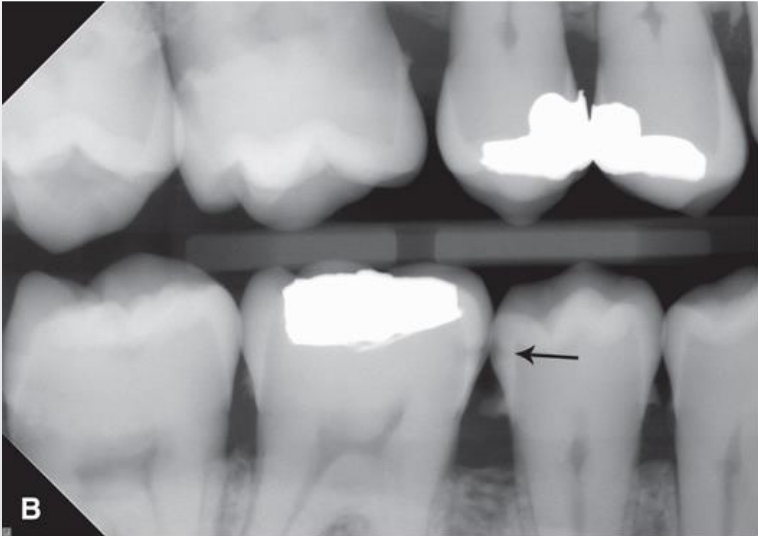

classify this lesion based on the ADA caries classification system

D3